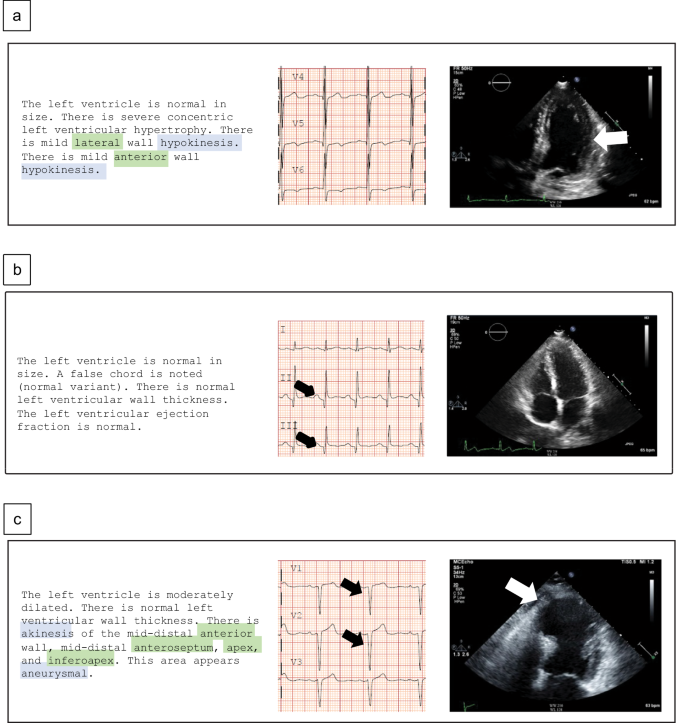

The clinical records for electrocardiogram interpretations and echocardiogram reports were obtained as unstructured text. We developed a novel scalable approach using NLP to objectively assign ground truth labels of WMA from echocardiography reports, and qualitative myocardial dysfunction patterns from ECG interpretations. This approach enabled us to address the challenge of obtaining expert labels in our large echocardiographic and ECG databases, which are larger than others in the literature22,23,24. Briefly, the NLP used customized regular expression scripts in Python v3.7, and provided an accuracy of 100% for extracting the WMA label when it was documented in the clinical interpretation of the echocardiogram. The accuracy of the NLP engine was analyzed by three expert reviewers in a random subpopulation of 100 studies selected from the test set and not used for engine development. As proof of concept, Fig. 2 illustrates NLP classification of echocardiography reports (left column), associated with raw ECGs (center), and echocardiograms (right) for three patients of the cohort. In Fig. 2a, a Black man in his 60s is shown with a history of cerebrovascular accident/stroke (CVA), heart failure (HF), and hypertension (HTN). An expert echocardiography report (ground truth) showed lateral (white arrow) and anterior hypokinesis (Supplementary Movie 1). No Q waves were visible on ECG or stated in its interpretation. ECG-WMA-Net (described below) correctly labeled WMA. Figure 2b shows a Hispanic male in his forties with type-2 diabetes mellitus undergoing chemotherapy for acute myelogenous leukemia had Q waves (black arrows) without echocardiographic abnormalities. ECG-WMA-Net classified normal wall motion. Finally, Fig. 2c shows a White female in her sixties with anterior myocardial infarction (MI) had an echocardiogram read as akinesis of the mid-distal anterior wall, anteroseptum, and inferoapex. In this case, the ECG report read sinus rhythm with probable old anteroseptal infarct (black arrows), and ECG-WMA-Net classified abnormal wall motion.

a A black man in his sixties without Q waves on ECG but with mild anterior and lateral WMA (white arrow) (ECG-WMA-net true positive). b A Hispanic man in his forties with Q waves on ECG but without WMAs on echocardiogram (ECG-WMA-Net true negative). c A female in her sixties with anterior and lateral Q waves (black arrows) on ECG and akinesis of the apex and mid-distal anterior and inferior walls (white arrow). Green text highlights show language tagged for location, and blue text highlights show language tagged for abnormalities.